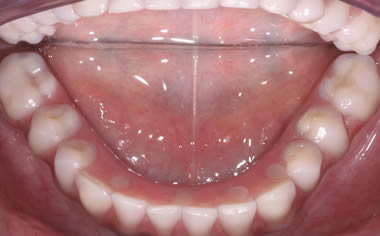

Full arches of teeth replaced by dental implants

Case One (5 images)

Full set of lower teeth fixed onto five dental implants.